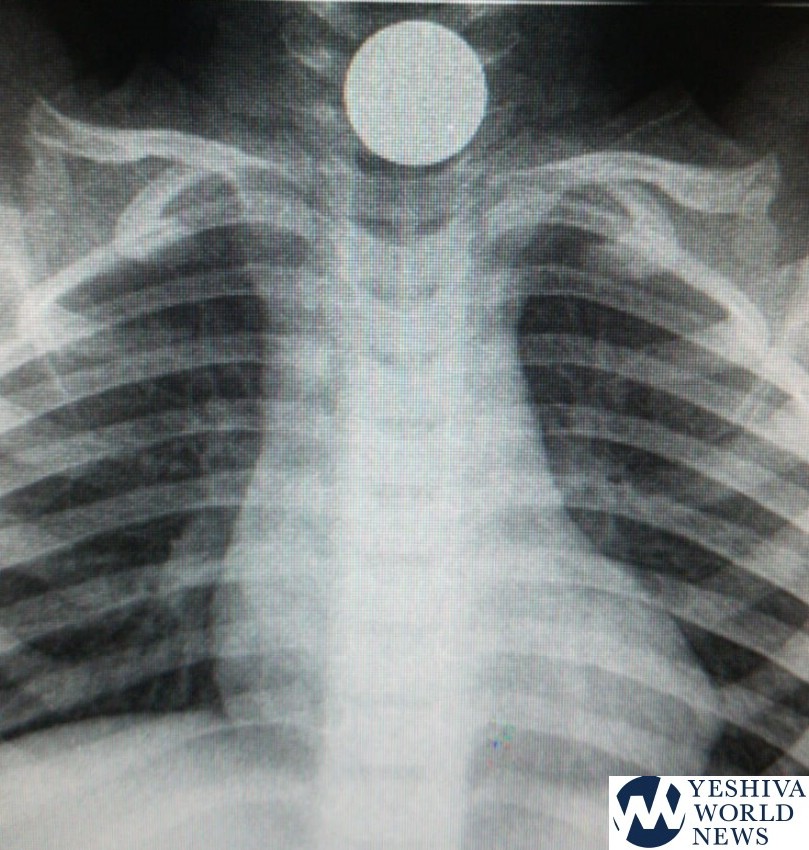

Doctors at a Terem emergency clinic in Carmiel treated a two-year-old child with a NIS 10 coin struck in his throat. He was brought in to the emergency clinic by his parents, who realized he was in pain and something was bothering him.

When they arrived at the Terem clinic, the child was checked and it appeared that he had a foreign object lodged in his throat, as was confirmed by x-ray.